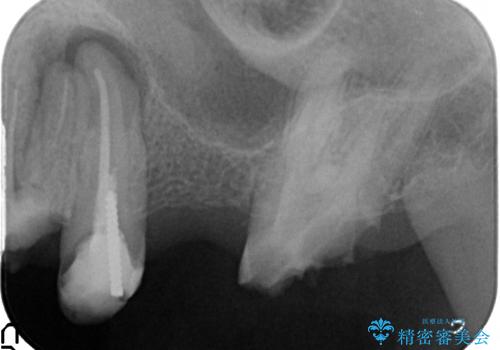

- 歯がない左側でものが咬めず、右側で咬むと歯が痛むので診て欲しいといらっしゃった方の症例です。

根尖病変が認められる歯は再根管治療を行い、歯根が破折していた左上4は抜歯しました。

インプラントは希望されなかったため、左側は1番から7番のロングスパンブリッジによる補綴を行いました。